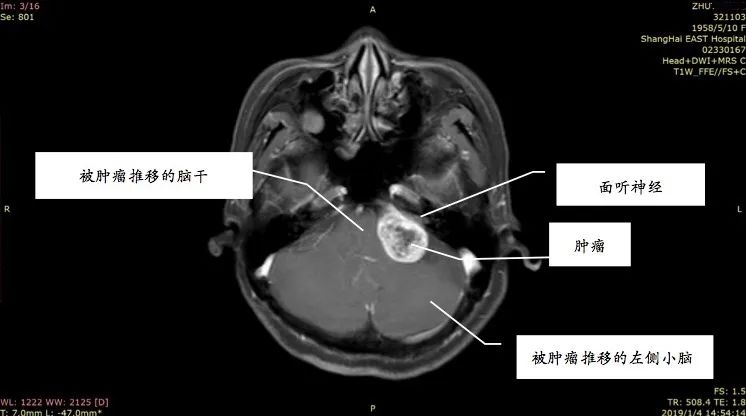

姚先生打电话时总听不清对方讲话,右边耳朵像有蜜蜂在飞,发出嗡嗡的声音。起初并没太在意,以为是工作繁忙劳累或情绪紧张,休息一会儿也就好了。前段时间他感觉耳鸣越来越厉害,并且还出现听力下降、失眠等症状,到医院做了头部的核磁共振增强扫描,发现他患上了听神经瘤。

听神经瘤是指起源于听神经鞘的肿瘤,为良性肿瘤,确切的称谓应是听神经鞘瘤,是常见颅内肿瘤之一。事实上,三分之二以上的人都出现过耳鸣的现象。那么,普通的耳鸣、脑中风的耳鸣与听神经瘤的耳鸣又有何区别呢?

听神经瘤引发的耳鸣

主要是单侧耳鸣,且音调较高,类似蝉鸣声、蟋蟀声,或者金属磨擦声。随着肿瘤越来越大,就可能压迫到周围神经,还也可能出现面部麻木、面肌痉挛、感觉异常、头晕,甚至走路不稳、瘫痪等类似脑中风的症状,且各项症状持续加重没有缓解。

据统计,临床上57%的听神经瘤患者会出现耳鸣等症状,其中26%的患者表现为突发性耳聋。随着肿瘤的生长,患者可能出现听力下降,甚至完全消失。但也不用太恐慌,听神经瘤只要及时接受科学治疗,并不会对患者造成严重危害。只要能够及时手术,切除肿瘤,患者多数可以获得较好的预后,并且听力有可能恢复。